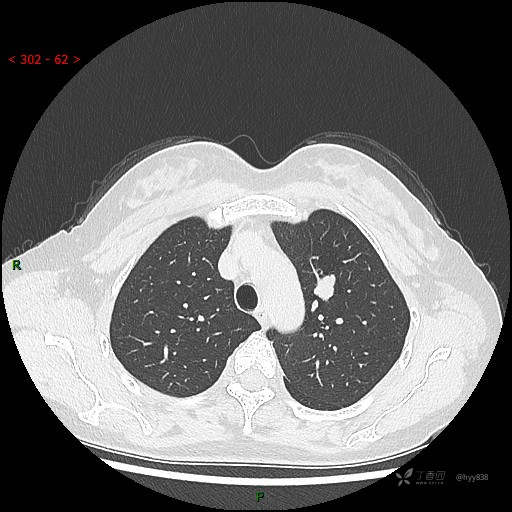

胸部CT平扫